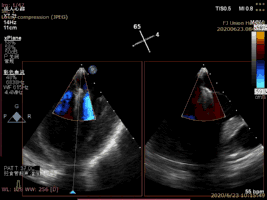

病例2术后二尖瓣反流为轻度